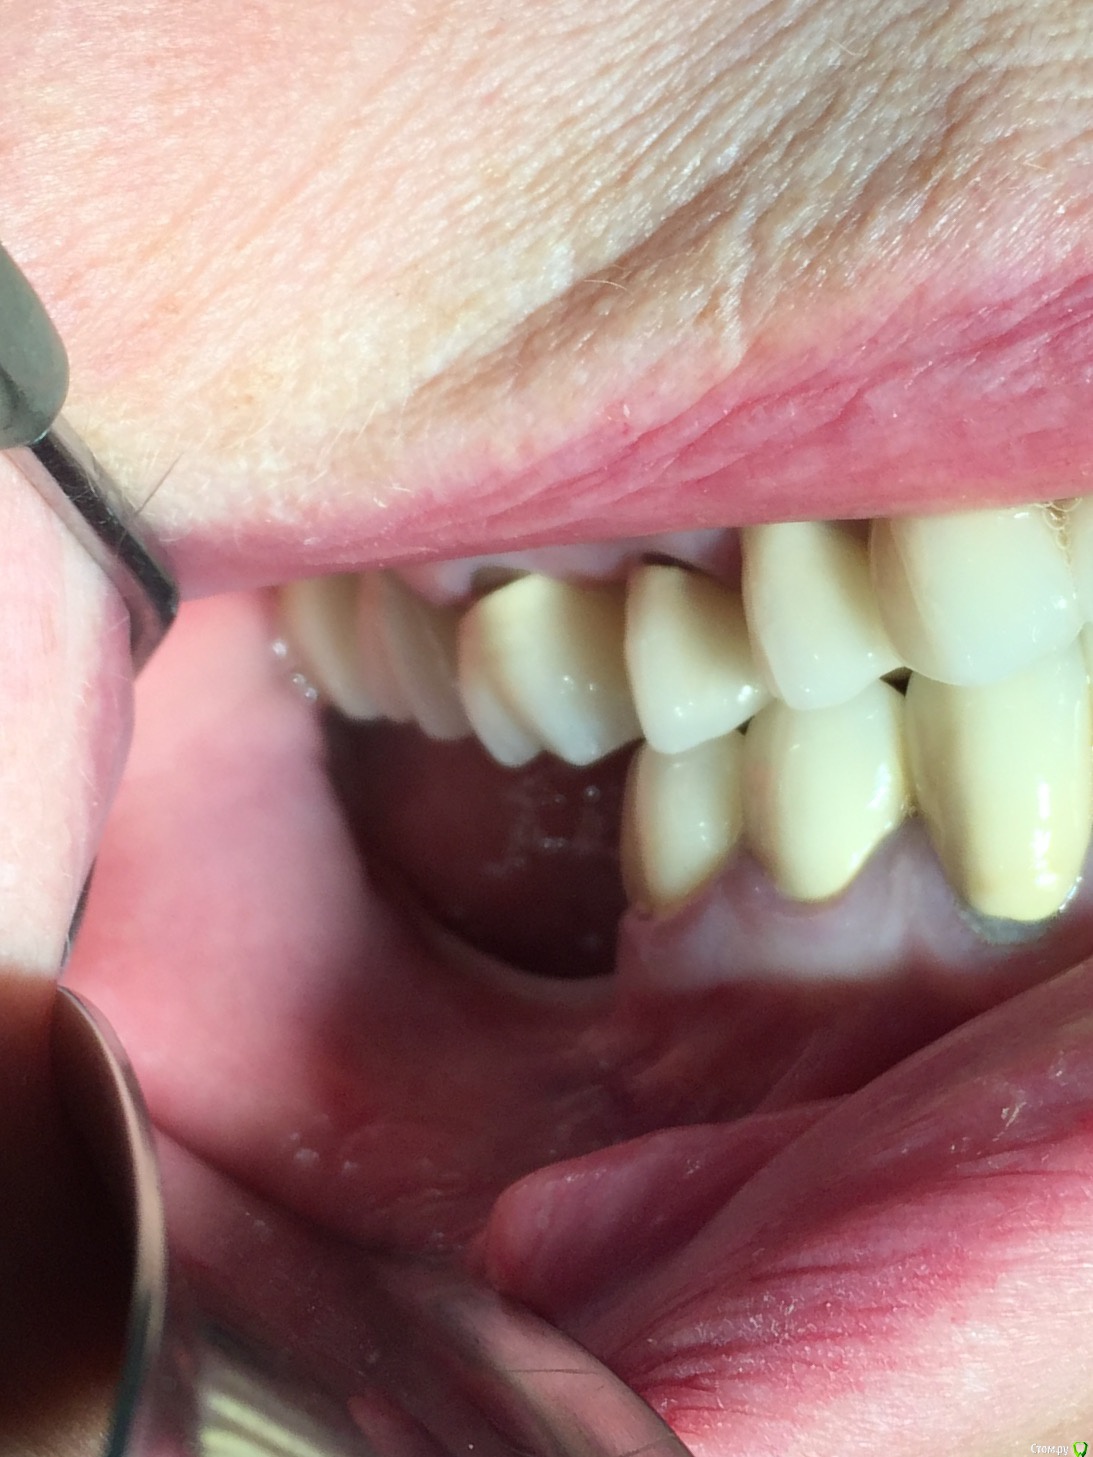

Популярный пост Глеб Митрофанов Опубликовано 22 октября, 2015 Популярный пост Поделиться Опубликовано 22 октября, 2015 (изменено) Горизонтальное расщепление Изменено 22 октября, 2015 пользователем Глеб Митрофанов 26 Ссылка на комментарий

carloss Опубликовано 22 октября, 2015 Поделиться Опубликовано 22 октября, 2015 (изменено) круто! а срезы кт есть в этой области? и откуда треугольный ламинат брали, который в щели? Изменено 22 октября, 2015 пользователем carloss Ссылка на комментарий

Глеб Митрофанов Опубликовано 22 октября, 2015 Автор Поделиться Опубликовано 22 октября, 2015 круто! а срезы кт есть в этой области? и откуда треугольный ламинат брали, который в щели?Срезы есть , в телефоне найду , прикреплю . Ламинатик получился , путём истончение треснувшей крыши в дистальном отделе , думаю чего добру пропадать , заклинил его и винтом на всякий случай . Ссылка на комментарий